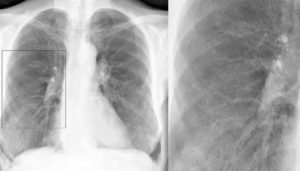

В отличие от острого, хронический бронхит выглядит на снимке следующим образом:

- разрастание фиброзной ткани и наличие малоструктурных корней;

- деформация или ярко выраженный рисунок;

- стенки бронхов частично утолщены;

- наличие расплывчатых границ.

Это основные моменты, отличающие хроническое заболевание бронхов от его острой формы.